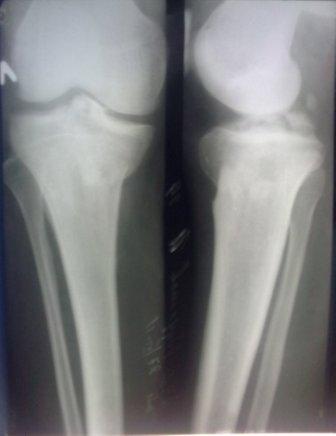

Здравствуйте уважаемые коллеги!Сегодня обратился больной 35л. Травму получил 3 мес.назад, упал в яму, лечился в отдаленном районе гипсовой повязкой, 1 месяц назад гипс сняли , и больной начал ходить с нагрузкой, постепенно появилась деформация коленного сустава, неустойчивость и боли. Локально: деформация коленного сустава, голень смещена кзади- типа подвывиха, разгибание 170гр. Сгибание 150гр.симптомов повреждение коллатеральных и крестообразных связок определить не удается из-за боли и контрактуры. Первичных снимков пока нет, обещали принести, имеется снимки через 2 месяца после травмы без гипса, недельной давности снимки в прямой проекции и К Т. Похоже, что импрессия переднемедиальной части внутреннего мыщелка б/берцовой кости, отрыв межмыщелкового возвышения.

На снимке типичный перелом медиального тибиал плато с передним смещением (подвывих) по Schatzker IV. Консервативное лечение без медиальной опоры не может удержать деформирующие силы, и из-за вторичного смещения мыщелка конечность смещается в варус. Кроме передних смещений еще встречаются сложные фронтальные варианты переломов, и тогда голень подвывихивается кпереди.

А в данном случае мыщелок сросся со смещением кпереди и ротирован. За счет интактной наружной колонны опороспособность конечности сохранена, но остается варус и экстензия конечности. Для предоперационного расчета необходимо сделать на всю длину конечности рентгенограмму, а в остром периоде КТ и 3-мерный снимок помогут лучше ориентироваться в характере перелома.